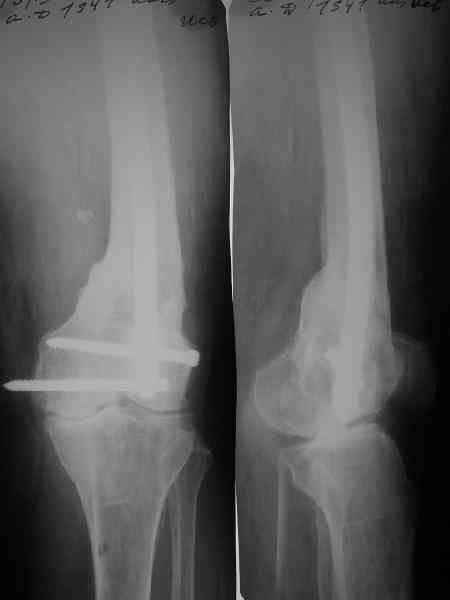

Спасибо. Прооперировали во вторник.

Выглядит красиво. А движения в колене какие были на столе?

Была контрактура и спаянный с суставной поверхностью надколенник. Сделали до синтеза редрессацию. Достигли почти полного объема движений.